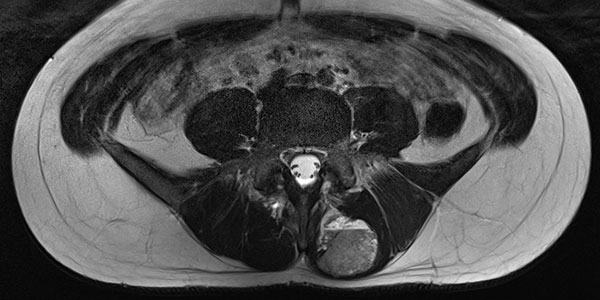

In the axial T2-weighted MRI sequence, the lesion is located in the erector spinae back muscles. Classic fluid-fluid level due to gravity-induced sedimentation effects with the patient lying still in the supine position in the MRI unit.